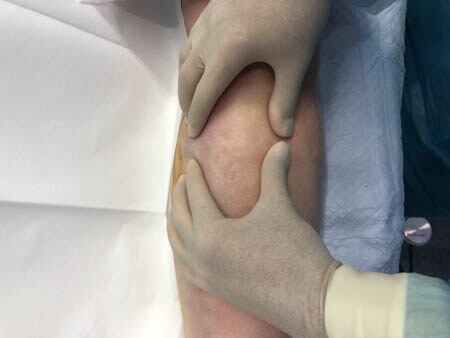

いつものように3Dタッチビュー(超音波)で

皮下脂肪層を評価してみましょう。

右ふくらはぎ

↓ ↓ ↓

上の画像の部分の皮下脂肪層をつまんでみましょう。